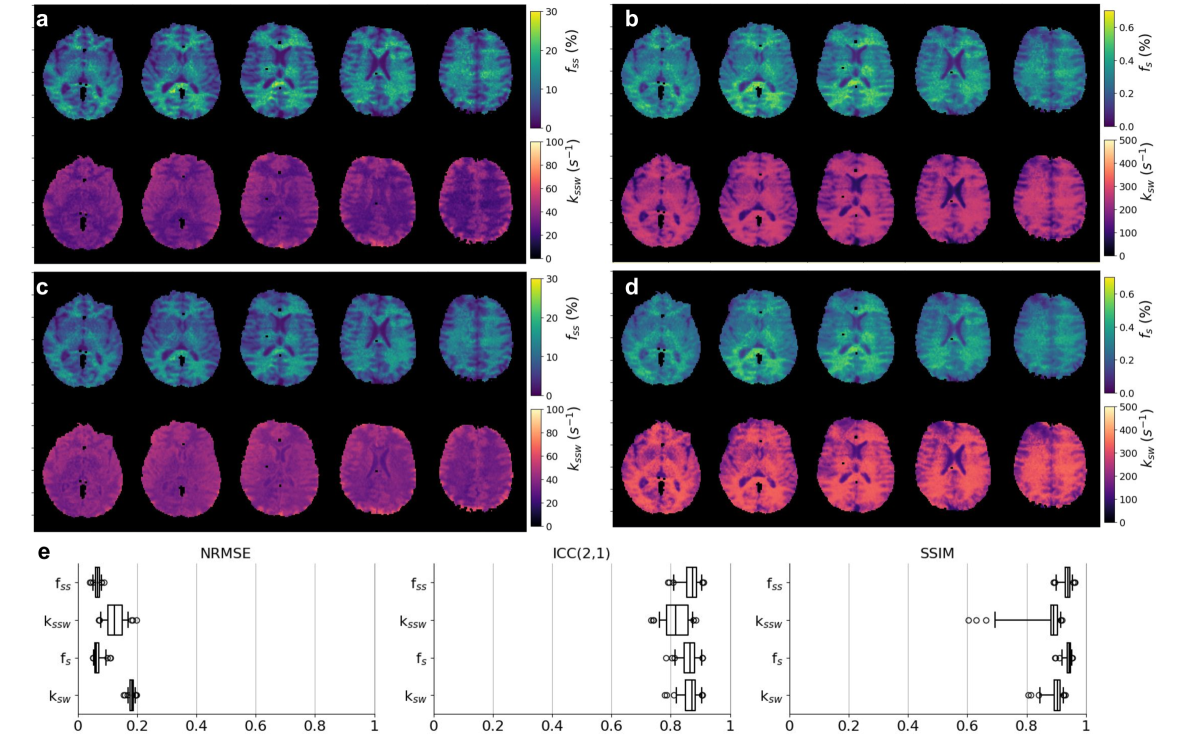

The joint fit and training of the NBMF produced a neural reconstructor, optimized on a single subject. We then re-applied the trained reconstructors to additional subjects in a fast inference mode. A representative example comparing the parameter maps obtained from single-subject NBMF with those obtained by a rapid reconstructor reuse is shown in Fig. 5. The resulting agreement metrics (Fig. 5e) were as follows; NRMSE: 7±plus-or-minus\pm±1%, 12±plus-or-minus\pm±3%, 7±plus-or-minus\pm±1%, and 18±plus-or-minus\pm±1%; Intraclass correlation coefficient ICC(2,1): 0.87±plus-or-minus\pm±0.03, 0.82±plus-or-minus\pm±0.04, 0.86±plus-or-minus\pm±0.03, 0.86±plus-or-minus\pm±0.03; SSIM: 0.93±plus-or-minus\pm±0.02, 0.87±plus-or-minus\pm±0.07, 0.94±plus-or-minus\pm±0.01, 0.90±plus-or-minus\pm±0.03, for the fss, kssw, fs, and ksw, respectively. Additional analysis is provided in Supplementary Figure 4.

Figure 5: NBMF’s fitting mode vs. transfer mode. A comparison between the results of single-subject NBMF (a, b) and a real-time quantification of the same subject by inferring the neural reconstructor trained while fitting another one (c, d). A perceptually and quantitatively similar outputs were obtained for both semisolid-MT (a, c) and amide (b, d) parameter mapping. e. Similarity analysis using normalized root-mean-square (NRMSE), intraclass correlation coefficient (ICC(2,1), absolute agreement-assessing variant) and structural similarity index measure (SSIM), across all (n=50) processed brain slices.